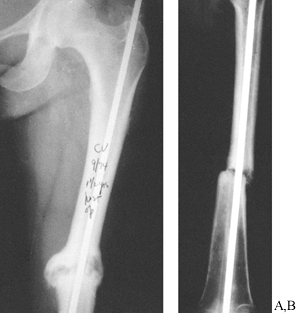

Figure 26.3. A:

Hypertrophic vascular nonunion 1.5 years after inadequate intramedullary nailing. Motion continues at the fracture with weight bearing. Bending, torsional, and shear stresses are not stabilized by the nail. B: Atrophic avascular nonunion 1 year after inadequate intramedullary nailing. Mechanical instability and avascularity have caused this nonunion. |